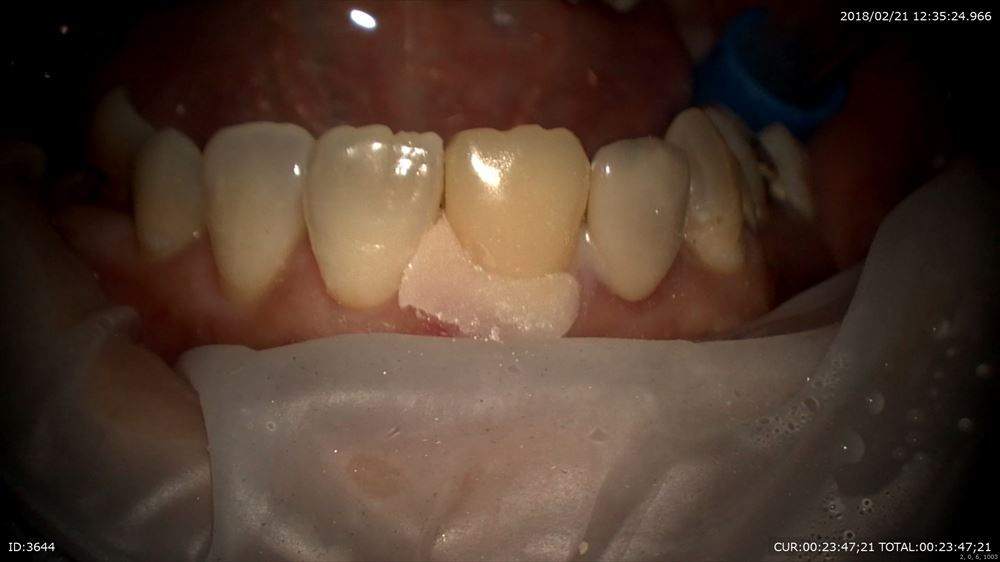

術前と術後

次の方は

「他院で説明がなくやっつけ仕事をされた」で来院

歯科ドックの後1.5時間カウンセリングでご納得いただき、

まず前歯から他院で折れているから抜かなければいけないかもとの事。外すと虫歯だらけ。。